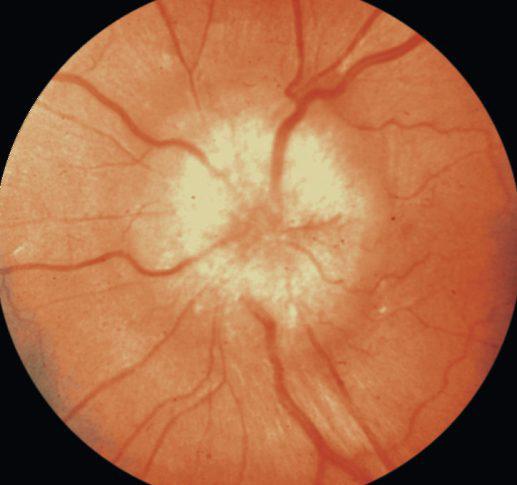

Определить застойный диск зрительного нерва на ранних стадиях можно только во время офтальмологического обследования, так как вокруг диска на сетчатке могут наблюдаться небольшие кровоизлияния.

- Офтальмоскопическое исследование – позволяет оценить состояние дисков зрительных нервов, сетчатки, сосудов, зрачков и глазного дна. С помощью офтальмоскопа можно обнаружить утолщения и сжатие вен сетчатой оболочки, а также отек и возможные кровоизлияния.